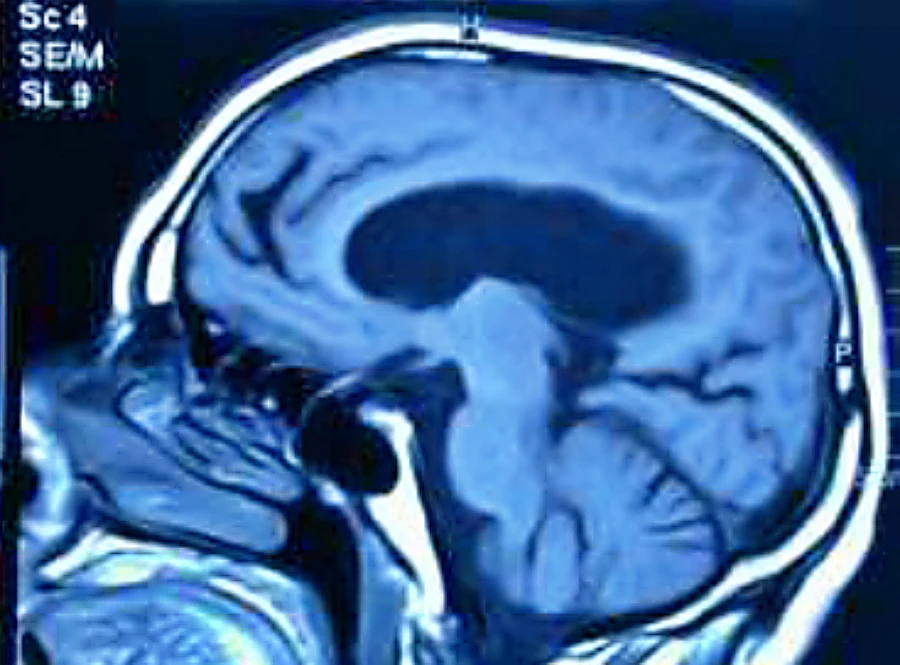

Este es el tema central de nuestra presentación: la hidrocefalia comunicante arreabsortiva del adulto, también conocida como HICA.

Esta condición se caracteriza por ser una hidrocefalia que aparece en la edad adulta, con dificultades en la reabsorción del líquido cefalorraquídeo pero manteniendo la comunicación entre los ventrículos y el espacio subaracnoideo.

Historia: Hakim y Adams en los Años 60

Esto fue descrito en los años 60 por Hakim y Adams y le dieron el nombre de hidrocefalia de presión normal del adulto porque veían que había aumento del tamaño ventricular, pero hasta ese momento se concebía que el aumento de tamaño se correspondía con una presión intracraneal alta. Curiosamente, al medirla, la presión era normal.

Ellos describieron que era porque se debía a un déficit de reabsorción de líquido cefalorraquídeo. También se puede llamar hidrocefalia arreabsortiva o comunicante.

1. Aumenta la presión intracraneal: Al principio, no se puede reabsorber y se van acumulando muy lentísimamente algo más de líquido en los ventrículos.

2. Aumenta la tensión de la pared ventricular: Como los globos, eso hace que aumente la tensión en las paredes ventriculares.

3. Incremento de la reabsorción transependimaria del LCR: El líquido cefalorraquídeo no se puede reabsorber por la vía normal y empieza a pasar a través del epéndima, que es una capa celular que recubre la pared interna de los ventrículos, y acaba entrando en el espacio extracelular cerebral. Ese espacio extracelular hace que las neuronas se vean más invadidas de agua y van a trabajar peor. Pero sin embargo es una salida para reabsorber el líquido cefalorraquídeo.

4. «Compensan» la hidrocefalia: Al final se acaba compensando la hidrocefalia en cuanto a no ser de una presión alta, sino que es una presión normal o incluso baja. Pero la tensión en las paredes ventriculares, especialmente en los lóbulos frontales, va a tener una repercusión clínica importante según la ley de Laplace: la tensión está directamente proporcional al radio, así que aunque haya una presión más baja, si hay un radio más alto, la tensión va a ser mayor.